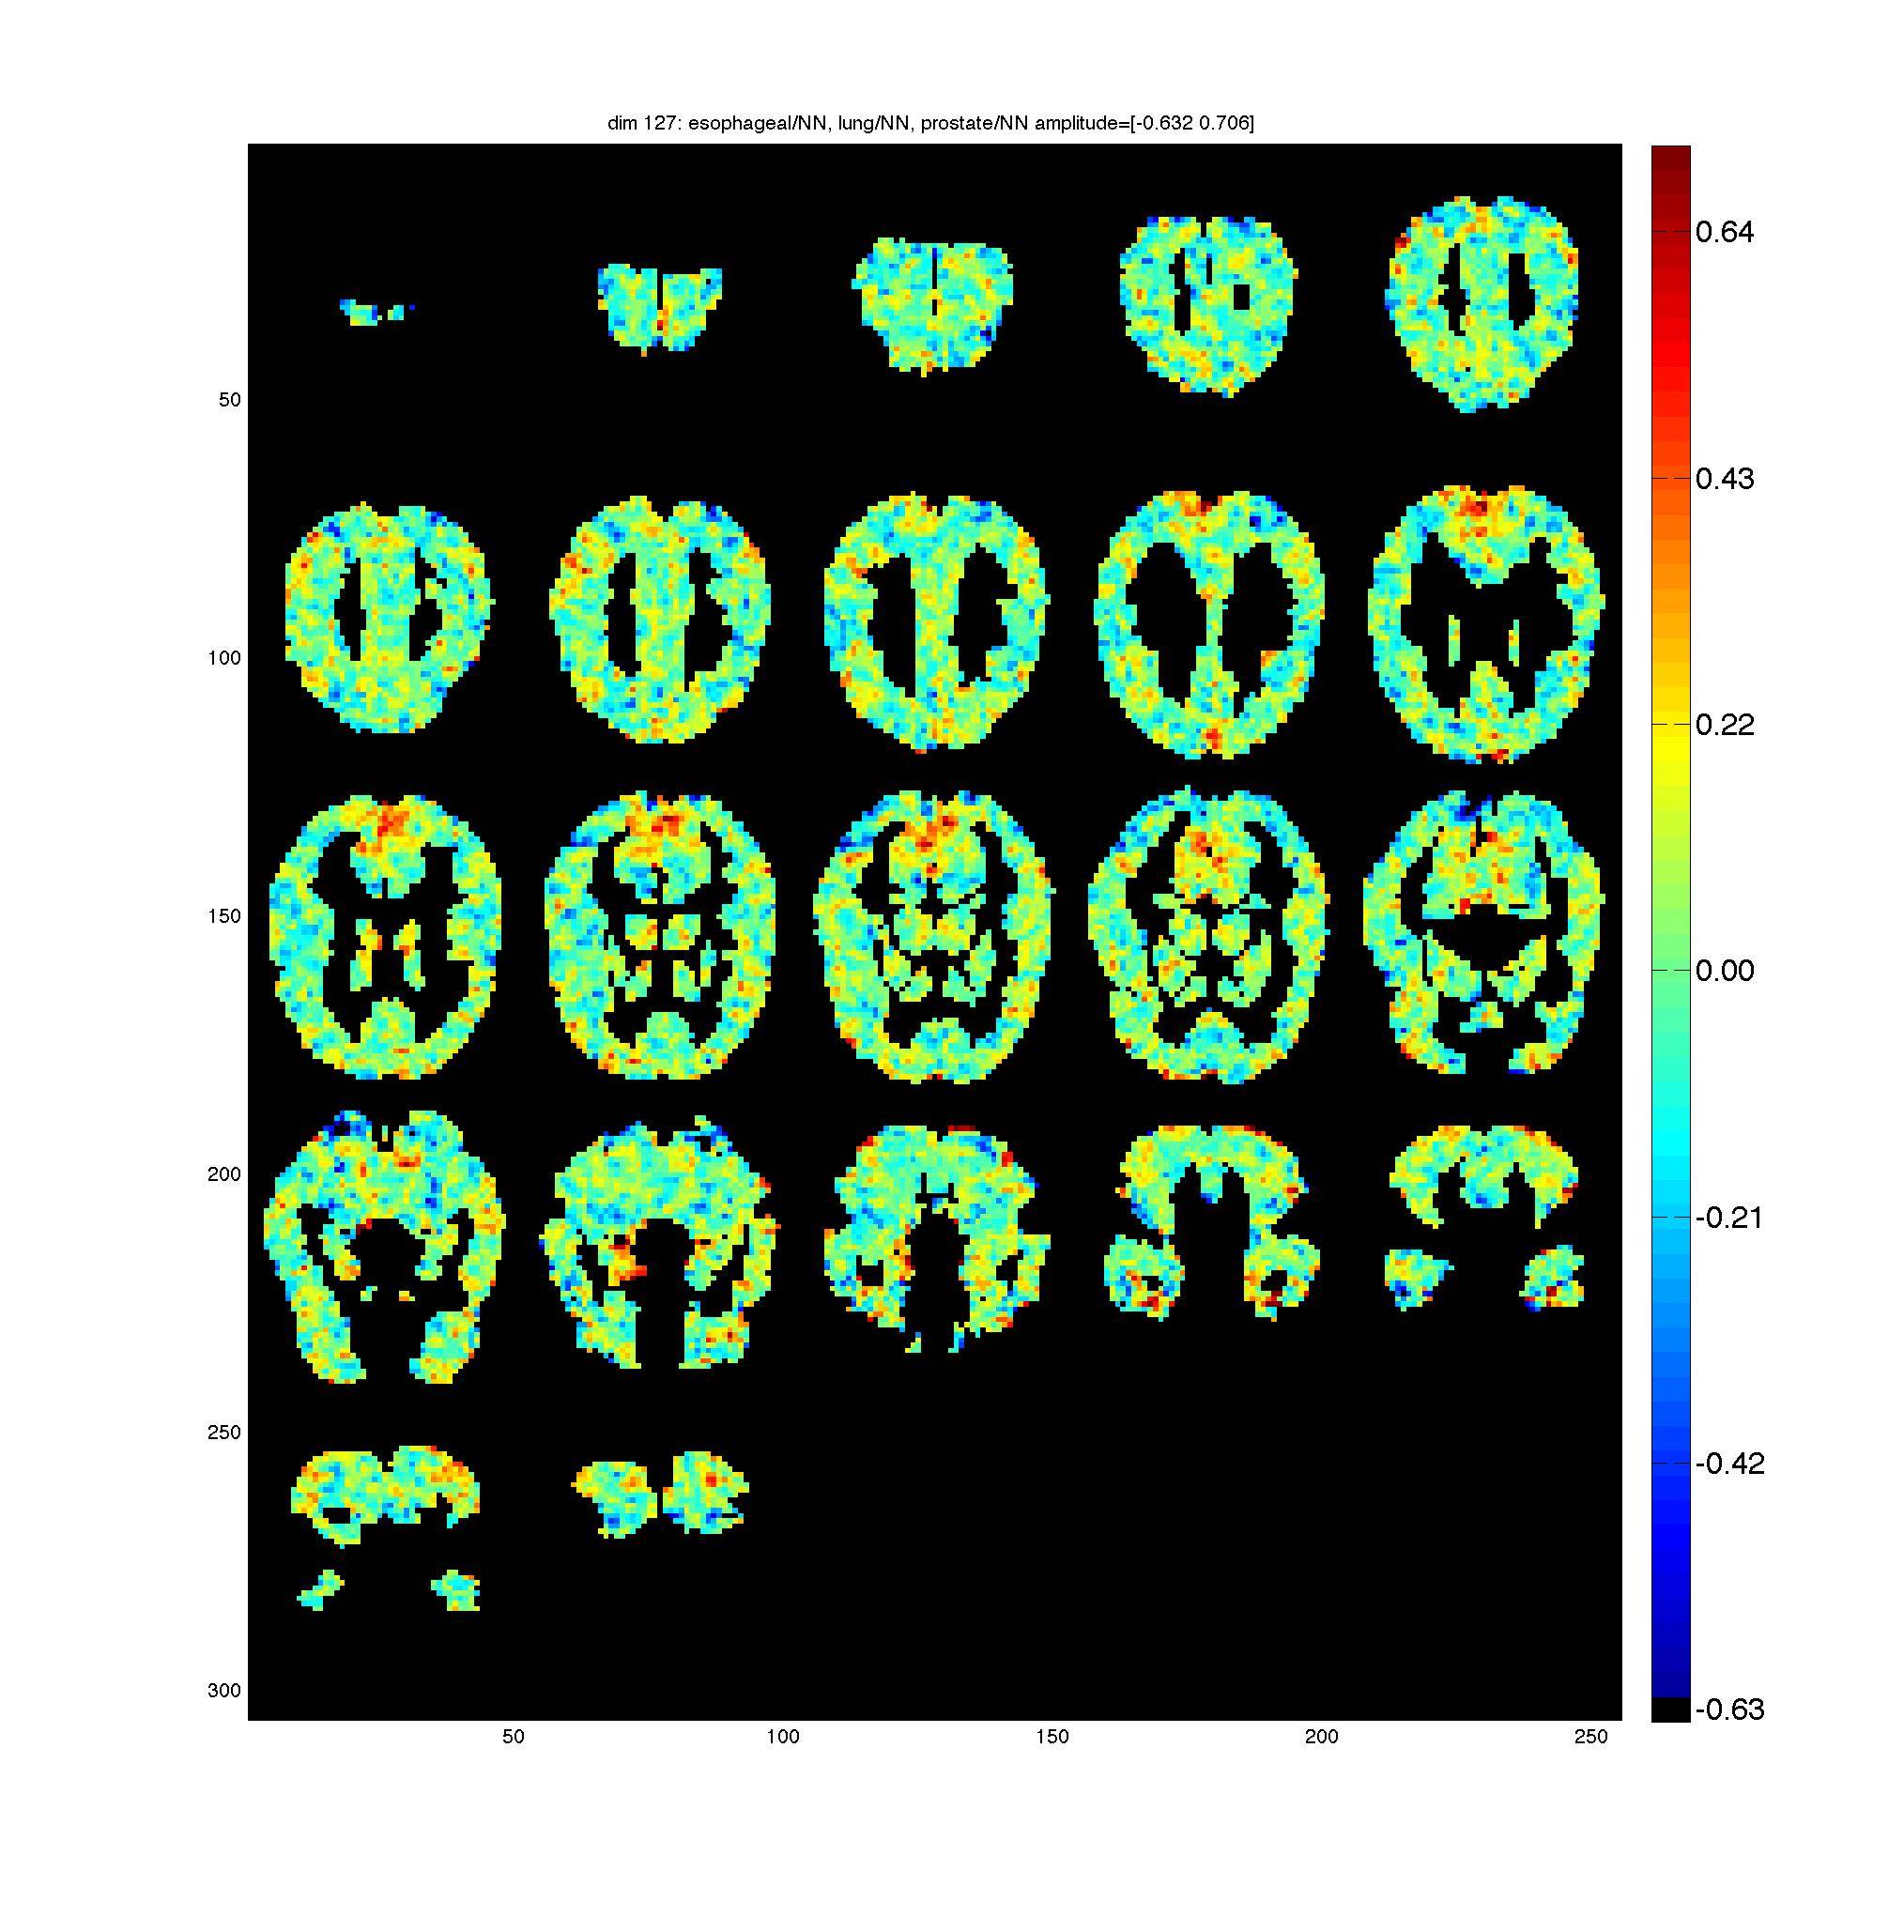

Below are the D^{(b)} maps for one fMRI subject.

Each dimension is

labeled with its top 3 scoring words which summarize the semantics of

the dimension. The last 11 dimensions correspond to the perceptual

features of the stimuli.

| dim 1: aroma/NN, scent/NN, fragrance/NN dim 2: mistake/NN, omission/NN, flaw/NN dim 3: strawberry/NN, raspberry/NN, cranberry/NN dim 4: cottages/NNS, villas/NNS, condominiums/NNS dim 5: bicycle/NN, bike/NN, scooter/NN dim 6: eyelashes/NNS, whiskers/NNS, eyebrows/NNS dim 7: trout/NN, pike/NN, sturgeon/NN dim 8: criminals/NNS, murderers/NNS, perpetrators/NNS dim 9: buffet/NN, brunch/NN, lunch/NN dim 10: refrigerator/NN, fridge/NN, dishwasher/NN dim 11: topologies/NNS, biomarkers/NNS, endpoints/NNS dim 12: determinant/NN, constituent/NN, drawback/NN dim 13: mites/NNS, nematodes/NNS, insects/NNS dim 14: princes/NNS, nobles/NNS, lords/NNS dim 15: chasm/NN, strait/NN, abyss/NN dim 16: nausea/NN, dizziness/NN, vomiting/NN dim 17: counselors/NNS, therapists/NNS, clinicians/NNS dim 18: echocardiogram/NN, annex/NN, almanac/NN dim 19: tens/NNS, dozens/NNS, billions/NNS dim 20: ann/NN, eta/NN, annotate/NN dim 21: downtime/NN, clutter/NN, hassles/NNS dim 22: imperatives/NNS, bent/NN, underpinnings/NNS dim 23: weirder/NN, wet/NN, moldy/NN dim 24: conclusions/NNS, assumptions/NNS, predictions/NNS dim 25: lamp/NN, lamps/NNS, torches/NNS dim 26: unix/NN, java/NN, cgi/NN dim 27: leopard/NN, giraffe/NN, hippo/NN dim 28: blockage/NN, narrowing/NN, vasoconstriction/NN dim 29: gala/NN, reunion/NN, symposium/NN dim 30: impairment/NN, retardation/NN, impairments/NNS dim 31: archiving/NN, browsing/NN, sharing/NN dim 32: self-determination/NN, individualism/NN, equality/NN dim 33: glaucoma/NN, lupus/NN, sclerosis/NN dim 34: canals/NNS, waterways/NNS, creeks/NNS dim 35: oppression/NN, exploitation/NN, slavery/NN dim 36: exemption/NN, injunction/NN, permit/NN dim 37: extremists/NNS, guerrillas/NNS, militias/NNS dim 38: vacationers/NNS, travellers/NNS, boaters/NNS dim 39: cliffs/NNS, outcrops/NNS, formations/NNS dim 40: gucci/NNS, vuitton/NN, chanel/NN dim 41: volleyball/NN, softball/NN, soccer/NN dim 42: otters/NNS, raccoons/NNS, herons/NNS dim 43: texas/NN, utah/NN, chicago/NN dim 44: ssh/NN, cvs/NNS, pipette/NN dim 45: consulate/NN, embassy/NN, expatriates/NNS dim 46: teaspoon/NN, tsp/NN, tablespoon/NN dim 47: gatherings/NNS, reunions/NNS, receptions/NNS dim 48: christianity/NN, libertarianism/NN, smallpox/NN dim 49: contaminants/NNS, toxins/NNS, chemicals/NNS dim 50: cherries/NNS, apricots/NNS, peaches/NNS dim 51: antibiotics/NNS, medicines/NNS, relievers/NNS dim 52: fraud/NN, bribery/NN, misconduct/NN dim 53: paucity/NN, ubiquity/NN, centrality/NN dim 54: freight/NN, tram/NN, subway/NN dim 55: stanza/NN, digit/NN, iteration/NN dim 56: negro/NN, schoolboy/NN, orphan/NNP dim 57: homer/NN, leadoff/NN, slam/NN dim 58: commonplace/NN, reliant/NN, pariah/NN dim 59: cornstarch/NN, buttermilk/NN, yolk/NN dim 60: indoors/NNS, afield/NN, backwards/NNS dim 61: grammar/NN, vocabulary/NN, idioms/NNS dim 62: scissors/NNS, saw/NN, pliers/NNS dim 63: toyota/NN, chrysler/NN, honda/NN dim 64: sophistication/NN, spontaneity/NN, elegance/NN dim 65: pussy/NN, tits/NNS, brunette/NN dim 66: spectroscopy/NN, scattering/NN, emission/NN dim 67: pours/NNS, drifts/NNS, accumulates/NNS dim 68: stew/NN, casserole/NN, burger/NN dim 69: pubs/NNS, cafes/NNS, nightclubs/NNS dim 70: vest/NN, apron/NN, blouse/NN dim 71: axle/NN, shaft/NN, clamp/NN dim 72: jug/NN, jar/NN, mug/NN dim 73: battering/NN, helm/NN, piss/NN dim 74: boats/NNS, yacht/NN, yachts/NNS dim 75: o/NN, a/NN, all/NN dim 76: year-old/NN, year-olds/NNS, v/NNP dim 77: counselor/NN, therapist/NN, clinician/NN dim 78: progesterone/NN, hormone/NN, estrogen/NN dim 79: electrician/NN, plumber/NN, inspector/NN dim 80: misdeeds/NNS, volition/NN, whim/NN dim 81: proclaims/NNS, advertises/NNS, posits/NNS dim 82: catastrophe/NN, calamity/NN, disaster/NN dim 83: ethnicities/NNS, nationalities/NNS, faiths/NNS dim 84: partake/NN, prosper/NN, discern/NN dim 85: cocaine/NN, heroin/NN, marijuana/NN dim 86: hillside/NN, alpine/NN, tundra/NN dim 87: gurus/NN, giants/NNS, moguls/NNS dim 88: outlays/NNS, surpluses/NNS, payoffs/NNS dim 89: wheat/NN, barley/NN, sorghum/NN dim 90: sister-in-law/NN, brother-in-law/NN, grandma/NN dim 91: frustrations/NNS, shortcomings/NNS, disappointments/NNS dim 92: sit-ups/NNS, pushups/NNS, push-ups/NNS dim 93: ventilation/NN, safeguards/NNS, aeration/NN dim 94: collaborators/NNS, donors/NNS, sponsors/NNS dim 95: rapes/NNS, kidnappings/NNS, murders/NNS dim 96: outpatient/NN, hospice/NN, inpatient/NN dim 97: decrease/NN, declines/NNS, decreases/NNS dim 98: sadness/NN, sorrow/NN, loneliness/NN dim 99: renderings/NNS, masterpieces/NNS, montage/NN dim 100: silo/NN, grandstand/NN, grotto/NN dim 101: proclamation/NN, warnings/NNS, plea/NN dim 102: alliances/NNS, friendships/NNS, collaborations/NNS dim 103: elucidation/NN, reassessment/NN, rethinking/NN dim 104: ny/NN, sc/NN, nc/NN dim 105: handicrafts/NNS, costumes/NNS, antiques/NNS dim 106: sitcoms/NNS, celebs/NNS, blockbusters/NNS dim 107: toddlers/NNS, newborns/NNS, adolescents/NNS dim 108: qualms/NNS, dreamt/NN, say/NN dim 109: laboring/NN, working-class/NN, transgender/NN dim 110: cushion/NN, sole/NN, liner/NN dim 111: yellow/NN, blue/NN, purple/NN dim 112: co-stars/NNS, godfather/NN, visage/NN dim 113: timer/NN, spreadsheet/NN, widget/NN dim 114: paneling/NN, siding/NN, woodwork/NN dim 115: igloo/NN, fast/NN, diatribe/NN dim 116: agility/NN, stamina/NN, resilience/NN dim 117: psi/NNS, megawatts/NNS, ppm/NN dim 118: thighs/NNS, hips/NNS, shoulders/NNS dim 119: appropriateness/NN, timeliness/NN, completeness/NN dim 120: blankets/NNS, pillows/NNS, linens/NNS dim 121: melodies/NNS, harmonies/NNS, riffs/NNS dim 122: hatching/NN, sundown/NN, thawing/NN dim 123: sweetie/NN, kitties/NNS, kitty/NN dim 124: gardens/NNS, lawns/NNS, courtyard/NN dim 125: clarinet/NN, saxophone/NN, cello/NN dim 126: reggae/NN, hip-hop/NN, techno/NN dim 127: esophageal/NN, lung/NN, prostate/NN dim 128: ankle/NN, elbow/NN, knee/NN dim 129: histone/NN, secretory/NN, effector/NN dim 130: fireball/NN, iceberg/NN, hunk/NN dim 131: fait/NN, tout/NN, les/NNS dim 132: carcinomas/NNS, tumors/NNS, tumours/NNS dim 133: orchid/NN, vine/NN, lotus/NN dim 134: biscuits/NNS, muffins/NNS, scones/NNS dim 135: fruition/NN, zenith/NN, pinnacle/NN dim 136: ze/NN, kan/NN, nu/NN dim 137: filmmaker/NN, playwright/NN, choreographer/NN dim 138: climber/NN, golfer/NN, diver/NN dim 139: concrete/NN, cement/NN, plaster/NN dim 140: arguing/NN, scrubbing/NN, cursing/NN dim 141: liposuction/NN, surgeries/NNS, augmentation/NN dim 142: scratches/NNS, scars/NNS, bruises/NNS dim 143: modifications/NNS, additions/NNS, revisions/NNS dim 144: lamb/NN, beef/NN, pork/NN dim 145: gratitude/NN, adoration/NN, admiration/NN dim 146: periphery/NN, midwest/NN, tropics/NNS dim 147: selfishness/NN, arrogance/NN, greed/NN dim 148: parsing/NN, partitioning/NN, scaling/NN dim 149: commanders/NNS, patrols/NNS, reservists/NNS dim 150: birch/NN, aspen/NN, pine/NN dim 151: trek/NN, hike/NN, commute/NN dim 152: vodka/NN, whisky/NN, scotch/NN dim 153: idealists/NNS, drunks/NNS, slates/NNS dim 154: royalties/NNS, stipend/NN, dues/NNS dim 155: influenza/NN, measles/NNS, meningitis/NN dim 156: receptors/NNS, kinases/NNS, binds/NNS dim 157: mathematician/NN, physicist/NN, sociologist/NN dim 158: obituary/NN, monograph/NN, preface/NN dim 159: recollections/NNS, passions/NNS, desires/NNS dim 160: michael/NN, peter/NN, robert/NN dim 161: estimating/NN, budgeting/NN, auditing/NN dim 162: carbohydrates/NNS, lipids/NNS, fats/NNS dim 163: mentoring/NN, recruitment/NN, outreach/NN dim 164: cows/NNS, cattle/NNS, herds/NNS dim 165: telephones/NNS, pagers/NNS, televisions/NNS dim 166: ko/NN, ay/NN, nga/NN dim 167: nutrient/NN, proviso/NN, subtype/NN dim 168: whirl/NN, blanche/NN, creeps/NNS dim 169: tractors/NNS, motorcycles/NNS, trucks/NNS dim 170: crates/NNS, trays/NNS, racks/NNS dim 171: jab/NN, glance/NN, swipe/NN dim 172: quot/NN, gt/NN, ll/NN dim 173: compartment/NN, doorway/NN, cavity/NN dim 174: resides/NNS, differs/NNS, complies/NNS dim 175: mailings/NNS, solicitations/NNS, invitations/NNS dim 176: adversity/NN, hardships/NNS, punishment/NN dim 177: satire/NN, jokes/NNS, thriller/NN dim 178: denomination/NN, congregations/NNS, seminary/NN dim 179: fangirl/NN, slacker/NN, wimp/NN dim 180: filmmakers/NNS, performers/NNS, songwriters/NNS dim 181: ferns/NNS, shrubs/NNS, vines/NNS dim 182: brokers/NNS, bankers/NNS, wholesalers/NNS dim 183: righteousness/NN, salvation/NN, deliverance/NN dim 184: cyclophosphamide/NN, outward/NN, nevirapine/NN dim 185: hcl/NN, prozac/NN, rx/NN dim 186: reticulum/NN, ketoacidosis/NN, codons/NNS dim 187: heterogeneity/NN, similarity/NN, similarities/NNS dim 188: mornings/NNS, afternoons/NNS, evenings/NNS dim 189: skepticism/NN, disapproval/NN, discontent/NN dim 190: time-series/NNS, initio/NN, microarray/NN dim 191: earrings/NNS, necklaces/NNS, bracelets/NNS dim 192: tampering/NN, flaming/NN, duplications/NNS dim 193: swoon/NN, amends/NNS, mockery/NN dim 194: blip/NN, tweak/NN, snip/NN dim 195: dormitories/NNS, restrooms/NNS, garages/NNS dim 196: telecom/NN, aerospace/NN, telecoms/NNS dim 197: soundtracks/NNS, recordings/NNS, broadcasts/NNS dim 198: westerners/NNS, leftists/NNS, republicans/NNS dim 199: antidote/NN, adjunct/NN, read/NN dim 200: quarterback/NN, pitcher/NN, lineman/NN dim 201: lawmakers/NNS, legislators/NNS, senators/NNS dim 202: kidneys/NNS, intestines/NNS, testes/NNS dim 203: outburst/NN, downpour/NN, bout/NN dim 204: tavern/NN, campsite/NN, winery/NN dim 205: grenades/NNS, rifles/NNS, pistols/NNS dim 206: frogs/NNS, reptiles/NNS, amphibians/NNS dim 207: wail/NN, whistling/NN, scream/NN dim 208: oysters/NNS, clams/NNS, prawns/NNS dim 209: coefficient/NN, velocities/NNS, coefficients/NNS dim 210: canoeing/NN, biking/NN, kayaking/NN dim 211: purchaser/NN, advertiser/NN, seller/NN dim 212: sellout/NN, panacea/NN, anathema/NN dim 213: blackjack/NN, roulette/NN, craps/NNS dim 214: triangle/NN, rectangle/NN, sphere/NN dim 215: tombs/NNS, temples/NNS, palaces/NNS dim 216: oregano/NN, rosemary/NN, thyme/NN dim 217: rodent/NN, rat/NN, insect/NN dim 218: sidewalk/NN, walkway/NN, embankment/NN dim 219: demons/NNS, ghosts/NNS, monsters/NNS dim 220: preservation/NN, restoration/NN, rebuilding/NN dim 221: beachfront/NN, beachside/NN, walt/NN dim 222: loft/NN, basement/NN, lounge/NN dim 223: seventies/NNS, eighties/NNS, nineties/NNS dim 224: sulfur/NN, chloride/NN, phosphate/NN dim 225: strife/NN, unrest/NN, confrontation/NN dim 226: vet/NN, neurologist/NN, nurse/NN dim 227: speckles/NNS, goo/NN, swirls/NNS dim 228: carb/NN, gourmet/NN, vegan/NN dim 229: aide/NN, backers/NNS, aides/NNS dim 230: grouse/NN, pheasant/NN, partridge/NN dim 231: treasurer/NN, provost/NN, superintendent/NN dim 232: nerve/NN, ligament/NN, tendon/NN dim 233: europe/NN, greece/NN, airfare/NN dim 234: sludge/NN, sewage/NN, wastes/NNS dim 235: stanzas/NNS, replicates/NNS, replications/NNS dim 236: intimidating/NN, daunting/NN, disgusting/NN dim 237: polyester/NN, silk/NN, wool/NN dim 238: patience/NN, honesty/NN, bravery/NN dim 239: apoptosis/NN, proliferation/NN, maturation/NN dim 240: requester/NN, noone/NN, original/NN dim 241: bioavailability/NN, permeability/NN, alkalinity/NN dim 242: confirmation/NN, submission/NN, enrollment/NN dim 243: craziness/NN, silliness/NN, bullshit/NN dim 244: storms/NNS, tornadoes/NNS, thunderstorms/NNS dim 245: economists/NNS, sociologists/NNS, anthropologists/NNS dim 246: shampoo/NN, lotion/NN, soap/NN dim 247: spinach/NN, cauliflower/NN, cabbage/NN dim 248: biochemistry/NN, microbiology/NN, pharmacology/NN dim 249: expulsion/NN, dissolution/NN, demise/NN dim 250: jackets/NNS, vests/NNS, sweaters/NNS dim 251: Word length, Word length, Word length dim 252: White pixel count, White pixel count, White pixel count dim 253: Internal details, Internal details, Internal details dim 254: Verticality, Verticality, Verticality dim 255: Horizontalness, Horizontalness, Horizontalness dim 256: Left-diagonalness, Left-diagonalness, Left-diagonalness dim 257: Right-diagonalness, Right-diagonalness, Right-diagonalness dim 258: Aspect-ratio: skinny->fat, Aspect-ratio: skinny->fat, Aspect-ratio: skinny->fat dim 259: Prickiliness, Prickiliness, Prickiliness dim 260: Line curviness, Line curviness, Line curviness dim 261: 3D curviness, 3D curviness, 3D curviness |